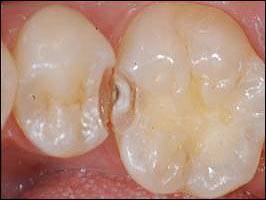

아말감의 단점은 일단 치아를 깎아야 하기 때문에 치질의 삭제가 많다. 실제로 환자의 치아는 위의 사진 모양으로만 썩은 것이 아니다. 아말감의 강도를 위해서는 썩지 않은 부분까지 삭제해서 위 사진과 같은 모양으로 형성을 해줘야만 한다.

다음으로 아말감 자체의 색이 좋지 않고 수복재 주변 치아를 변색시키기 때문에 비심미적이라는 단점 역시 가지고 있다. 마지막으로 인접치와 닿은 부분에서는 그 성능이 현저하게 떨어진다.